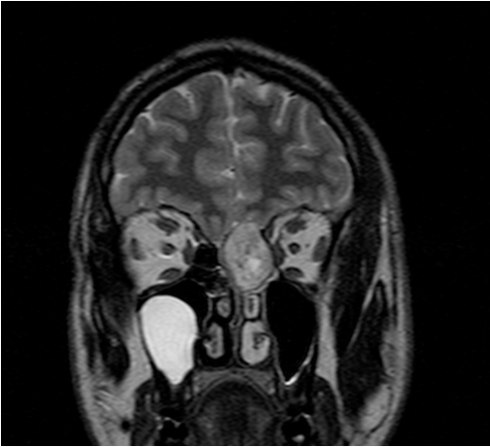

Las enfermedades de la base del cráneo requieren cirujanos expertos y procedimientos altamente específicos, considerando las dificultades anatómicas de la región y las importantes estructuras allí localizadas. En la Unidad Alergo·Rino tenemos una dilatada experiencia en el tratamiento de enfermedades tumorales y malformaciones que afectan a la base del cráneo. Somos expertos en el abordaje endoscópico mínimamente invasivo.

La Unidad dispone de un sistema de Navegación con imágenes de alta definición que aporta datos anatómicos en tres dimensiones para mejorar la orientación dentro del campo quirúrgico ayudando en los distintos pasos quirúrgicos y mejorando la seguridad. En nuestra Unidad tratamos todas las lesiones que afectan la base de cráneo tales como: tumores malignos de senos paranasales, angiofibroma juvenil, adenomas hipofisarios, cordomas, meningiomas, quistes de Rathke, y lesiones de la unión craneo-vertebral.